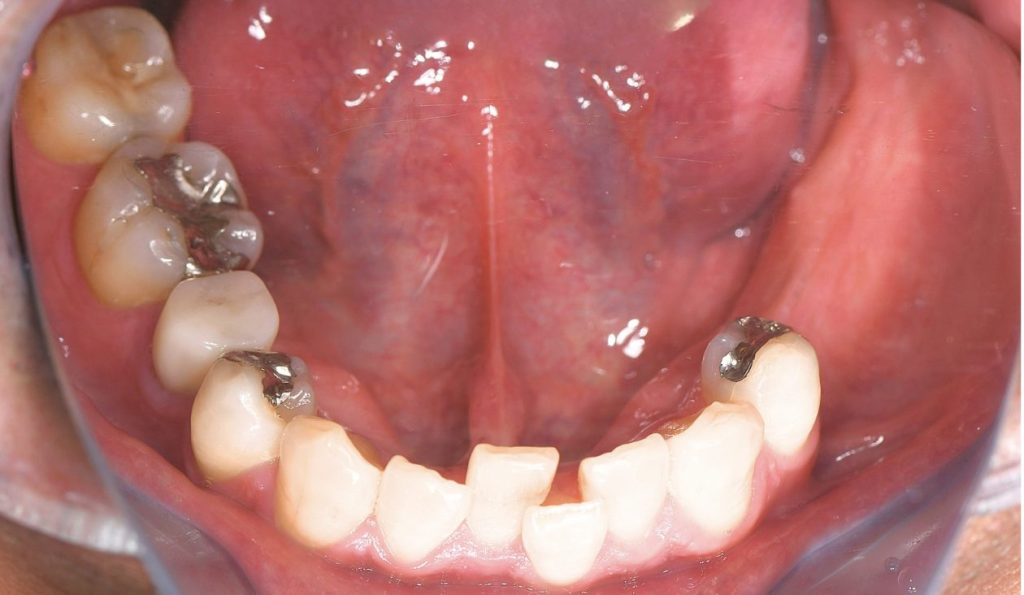

抜歯から3ヶ月経過後

初回来院後、定期的に検診・メンテナンスで来院されていたが、

初回来院から約1年後、左下5番に自発痛を認めた。

診査の結果、元々咬合力が非常に強く、う蝕により歯質が菲薄化(薄く脆弱化)した状態の歯牙が

咬合負荷に耐えきれず、歯根破折を発症していることを確認。

また、左下6遠心根についても構造的・機能的予後が不良と判断。